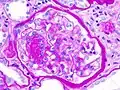

Гистопатологическая картина диабетического гломерулосклероза с нефротическим синдромом.